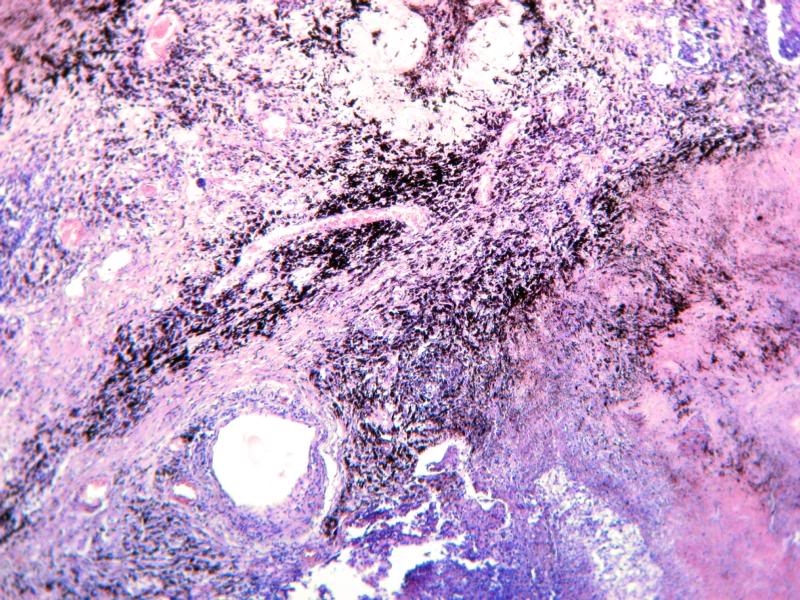

Ihr seht einen Lungenschnitt, der die Anthrakose (auch Staublunge) deutlich zeigt. Dabei handelt es sich um eine Staubinhalationskrankheit. Die vielen schwarzen Punkte sind mit kohlestäuben beladene Makrophagen. Ursache dieser Veränderung ist das häufige Einatmen von Stäuben z.B. aus Autoabgasen oder auch Zigarettenrauch. Diese Krankheit wurde erstmals bei den Arbeitern der Steinkohleminen festgestellt und erforscht.

Ich hoffe die Bilder gefallen euch. Sie sind zwar nicht ganz optimal, aber das wesentliche erkennt man. Zum Histologischen kann ich euch leider nicht mehr erzählen, dazu fehlt mir einfach das Wissen. Ich finde es aber trotzdem sehr interessant, sich diese Ablagerungen anzusehen. Die Bilder selbst wurden alle mit meiner A540 am Zeiss Standard gemacht und mit PSE 5.0 leicht nachbearbeitet.

Ich war schon sehr lange nicht mehr im Mikroskopie-Forum, habe aber gerade, dieses Diskussion zum Thema Staub-Lunge gesehen: Nein, gesunde Lungenbläschen sehen anders aus. Es ist nicht  wie auf dem obigen Bild nur mit schwarzen Einschlüssen. Für die Lungenfunktion ist eine große Oberfläche notwendig, die durch viele winzige Lungenbläschen (Alveolen) erzielt wird.  Bei der Staublunge ist dagegen ein großer Teil des Gewebes durch Bindegewebs-Strukturen ersetzt, die Oberfläche der Lungenbläschen ist darum nur noch klein. Dadurch ist die Lungenfunktion bei einer Staublunge stark beeinträchtigt.